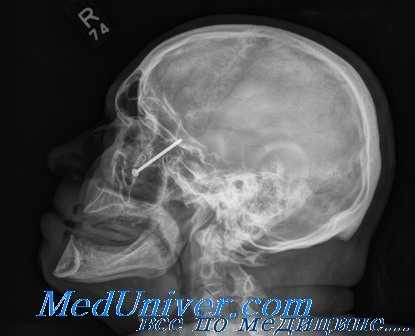

Естественно, что при рентгенологическом исследовании необходимо обратить внимание на наличие в глазнице инородных тел. Металлические осколки определяются легко, но нередко флегмона глазницы может быть обусловлена проникновением инородных тел, дающих мало интенсивную тень, как, например, дерево, стекло и т. д. На технически хорошо выполненных рентгенограммах в таких случаях иногда можно обнаружить едва диференцируемую тень инородного тела.

Глазное яблоко на рентгенограммах не диференцируется. Однако можно представить местоположение глазного яблока путем анализа нежных теней и просветлений, наблюдаемых в области глазницы, а также путем проекции глазного яблока на определенные костные пункты глазницы. Известный интерес представляют экспериментальные исследования авторов, изучавших рентгенологически на трупах проекцию глазного яблока на определенные костные пункты глазницы.

Воспалительные процессы в самом глазу не могут быть отражены на рентгенограммах, за исключением тех случаев, когда в глазу образуются очаги обызвествления. Так, иногда приходится наблюдать обызвествление хрусталика. Такой обызвествлениый хрусталик отчетливо выделяется на рентгенограмме. Если обызвествлен весь хрусталик, то на рентгенограмме он имеет почти правильную форму круга, периферическая зона которого даст более интенсивную тень, чем центральная. В литературе описаны случаи, когда такой обызвествлениый хрусталик принимался за инородное тело.